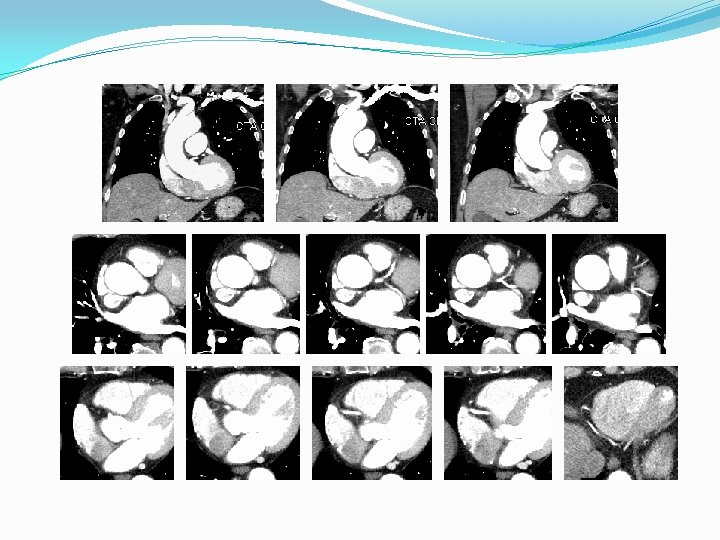

Ascending Aortic Aneurysm of Degenerative Etiology

Ascending Aortic Aneurysms Associated With Genetic Disorder